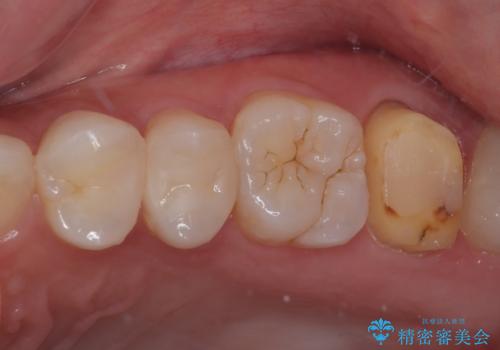

レジンが劣化してきた オールセラミッククラウン

- すごく前に治療したレジンがざらつくので治療したいとのことで来院された患者様です。十年ほど前に根管治療を行っており、症状は特に何もない状態でした。根管治療を行っている歯は咬合力に対して鈍くなり破折しやすくなるため、最終的には被せものによる補綴治療を行う必要があります。